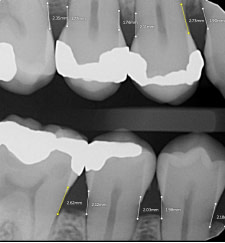

Bone Measurements

The system provides automated measurements from the crest of the bone to the cementoenamel junction (CEJ). These measurements are color-coded to indicate severity:

- White: 0-2.5 mm

- Yellow: 2.5-4 mm

- Amber: >4 mm

This feature is helpful for periodontal assessments, streamlining the process of identifying areas of bone loss. However, it's important to note that image angulation can affect the accuracy of these measurements, a limitation the system acknowledges.

I found these lines to be incredibly useful when describing patients' periodontal health. Cool feature, no doubt.